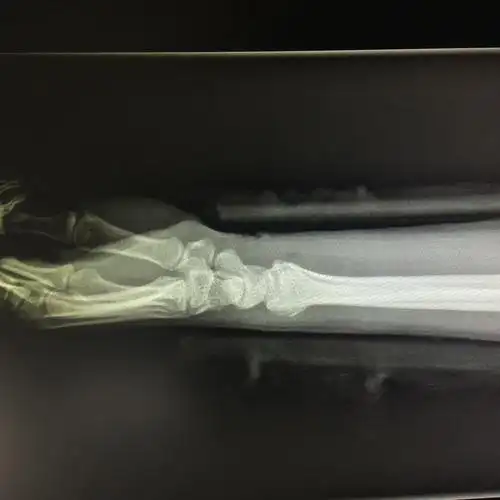

各位老师看看这个colles骨折复位可以不

一组colles骨折手法复位

患者女58岁左colles骨折